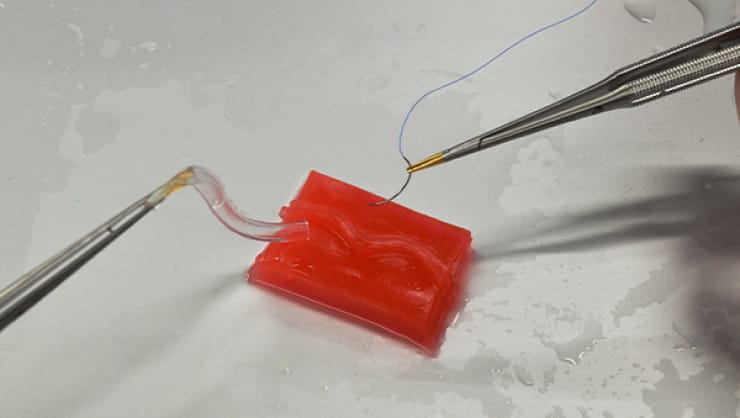

人体と同等の含水率のため、実臓器の触感や柔軟性など、リアルな生体感を得ることができる。

摩擦抵抗が低いため、デバイスをモデル内に通過させる際、生体と近い操作感を得ることが可能。高透明材のため、目視下でも、デバイスの挙動確認ができる。

ウレタンやシリコン製のモデルと組み合わせることで、幅広い領域での活用を実現。